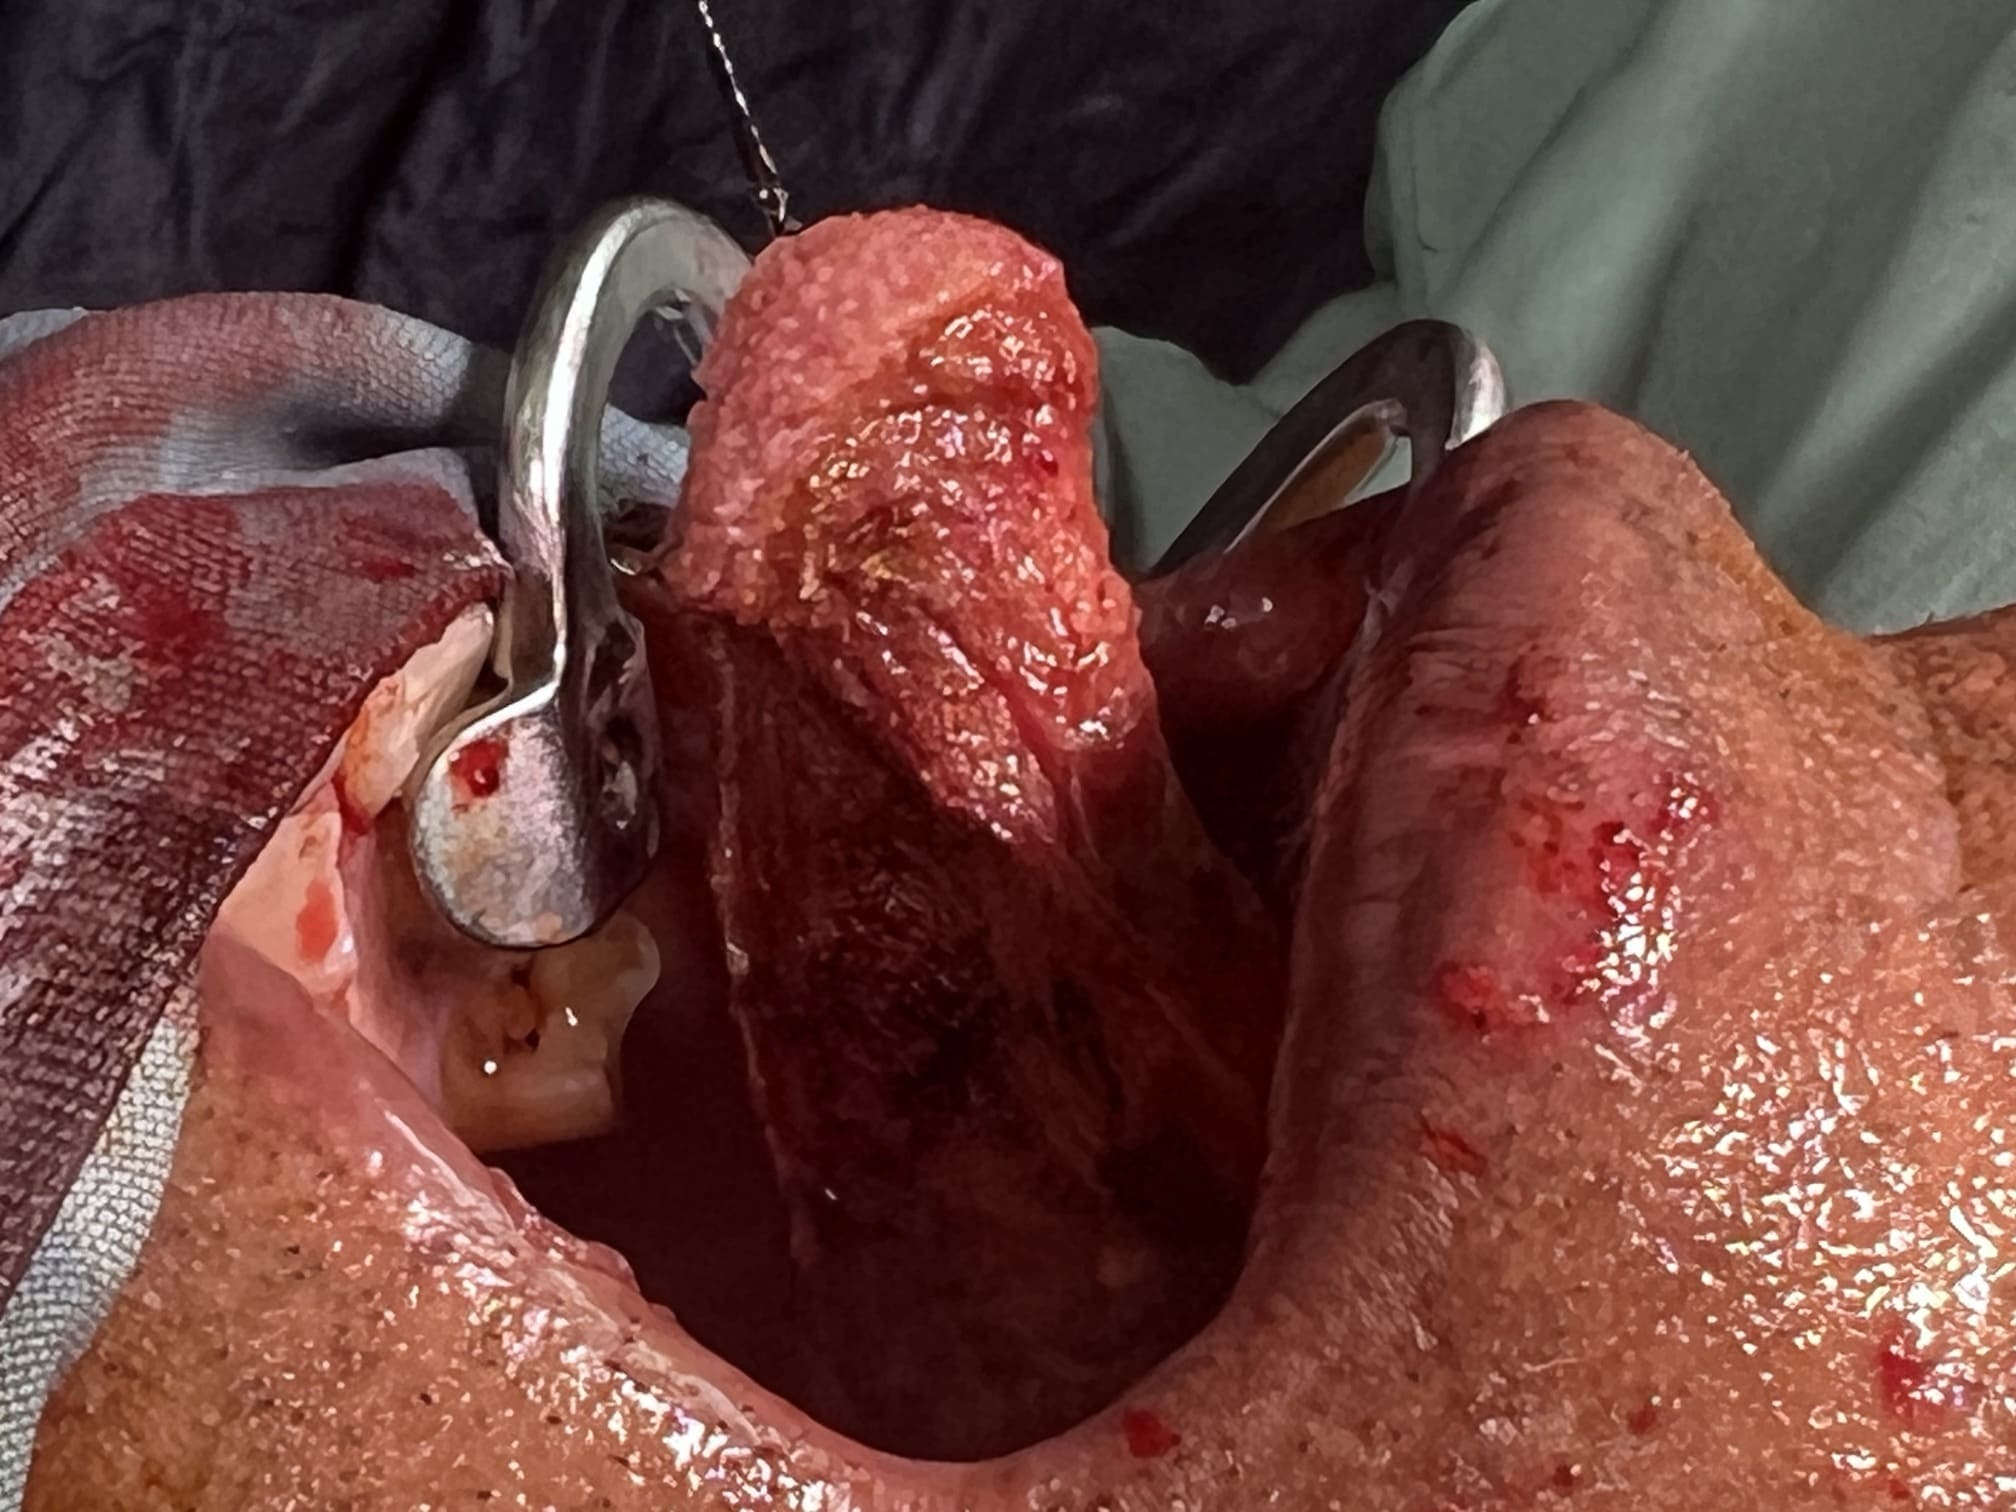

57 years old female suffering from left buccal mucosa growth involving left RNT and gingival surface of lip extending up to right angle mouth.left modified neck dissection with left distal segmental mandibulectomy with wide excision of left buccal mucosa with left RMT growth with excision gingival margin of lower lip with left pectoralis with right nasolabial flape done.

29-12-2025